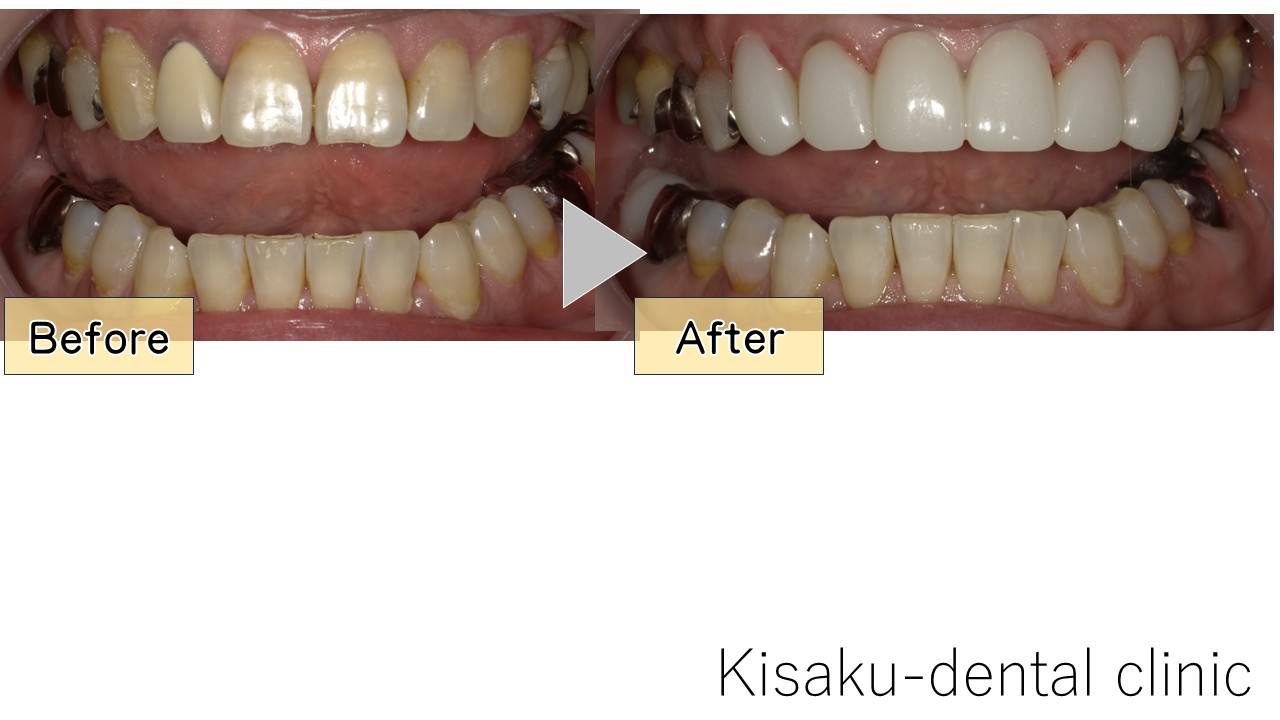

歯が黄色い・色が黒い気がした。

以前から気になっていたので

キレイにしたかった。

不安もあったが、以前と違いすぎて(良い意味で)

気持ちが明るくなった!

口元を気にせず話せる様になってうれしい!